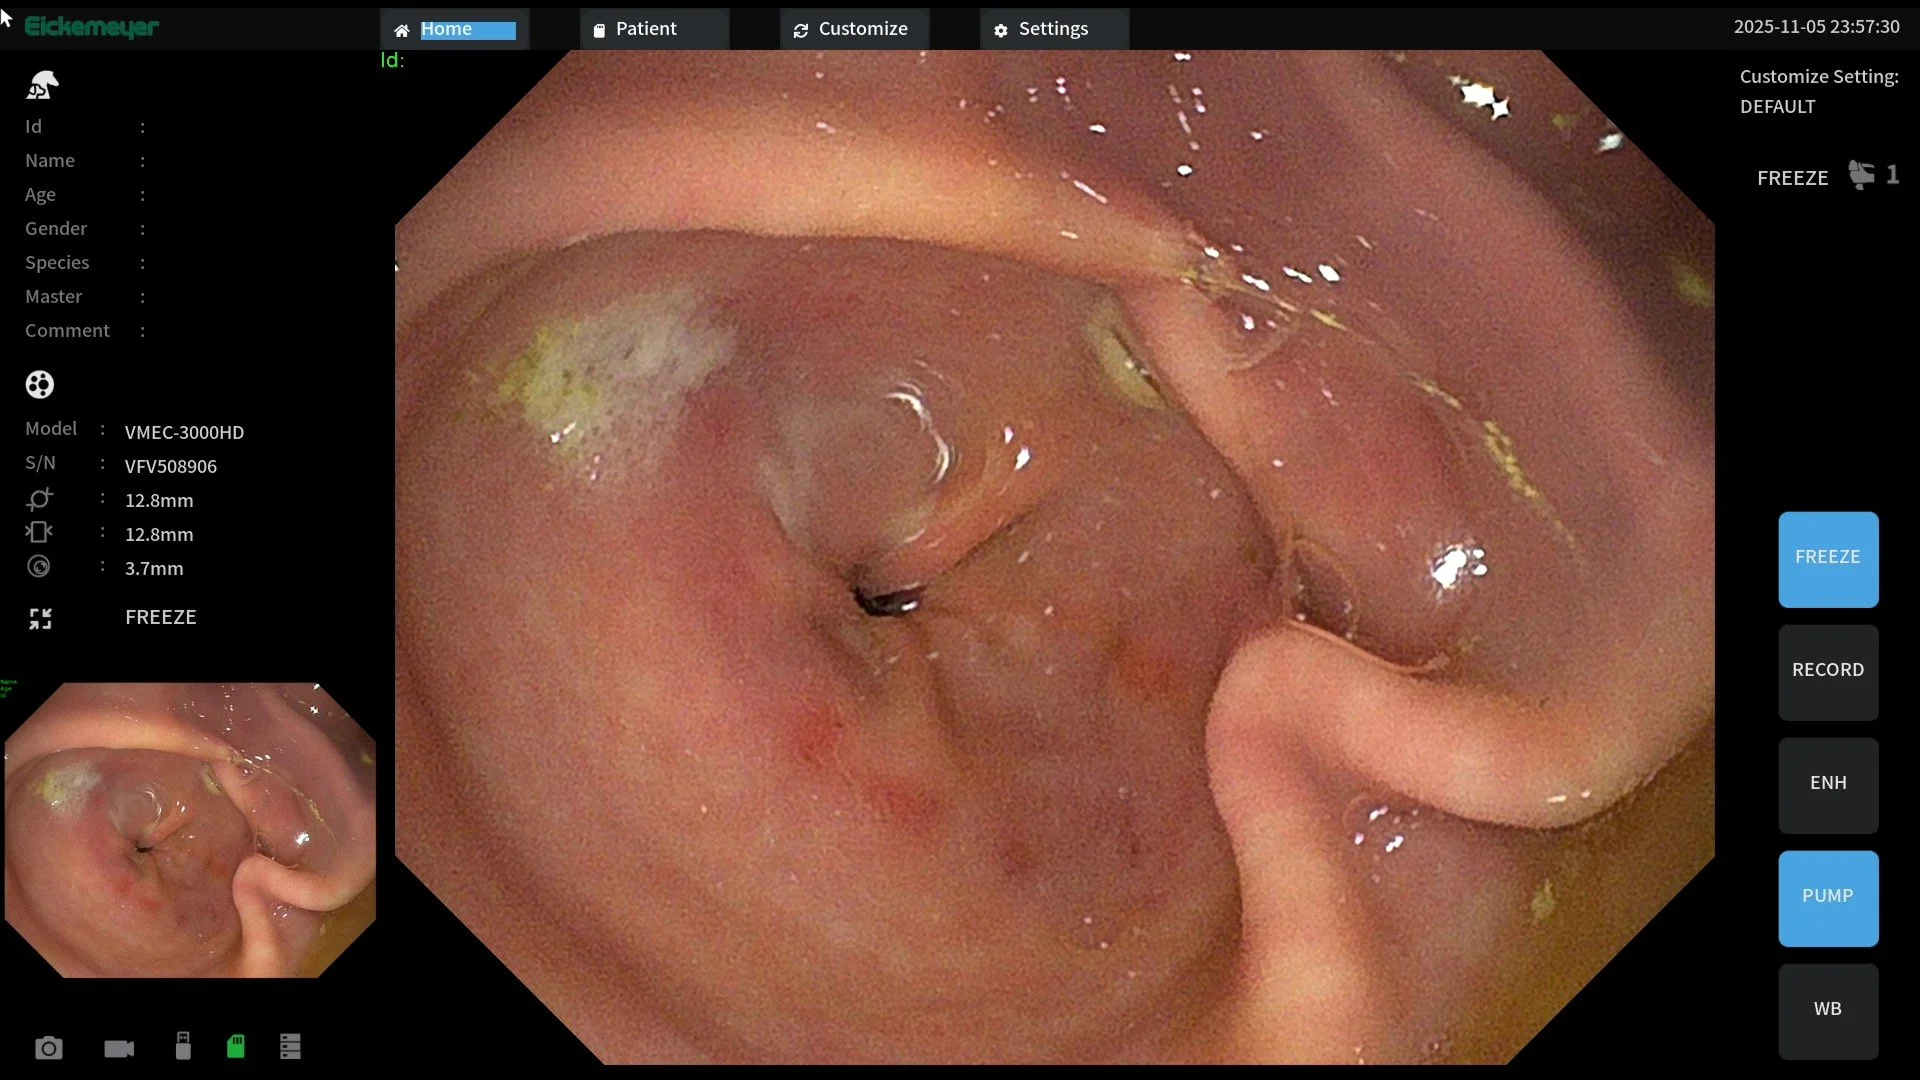

Gastroscopy is performed using a specialized flexible endoscope that is passed down through the horse's esophagus to directly visualize the stomach itself. Direct visualization allows diagnosis of the presence of ulceration, the location and the degree of ulceration – all important factors in treatment plans.